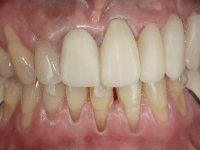

66-year-old male patient, non-smoker. It featured a 5-member metal-ceramic bridge with extreme mobility. Teeth 11 and 21 had infiltrated cervical margins. Both arches showed root exposure with signs of cervical abrasion. Composite resin “slots” were visible on the buccal surfaces of some mandibular teeth compatible with an orthodontic treatment with aligners that the patient was undergoing. After the imaging examination, it was found that the bridge's distal support, tooth 24, was irretrievably lost. The mesial pillars 11 and 21 had endodontic treatment and intraradicular posts. Teeth 25 and 26 also had endodontic treatment and extensive restorations in composite resin. In the lower jaw, two bridges were visible. In the third quadrant a 4-element bridge supported on tooth 35 and on 2 implants placed in the location of teeth 36 and 37. In the fourth quadrant a 3-element bridge supported on tooth 45 and an implant placed in the location of tooth 46. The patient presented a thick gingival phenotype and very good oral hygiene.

A temporary acrylic bridge made in the laboratory with 7 elements was made, with teeth 11,21, 25 and 26 as pillars. The old bridge was removed and tooth 24 was extracted. The provisional bridge after relining was cemented in the mouth. Two implants were placed in the teeth 22 and 24 and 3 months after this intervention an impression was made to make a temporary bridge screwed over the implants and cemented to the teeth. The bridge was placed in the mouth and teeth 25 and 26 were extracted. 3 months later, surgery was performed to fill the maxillary sinus and 6 months later the implant was placed in the location of tooth 26. After osseointegration of this implant, the final impression was made for the final work. The bridge over the implants was permanently screwed on and the bridge over the teeth was cemented with resin-reinforced glass ionomer cement.